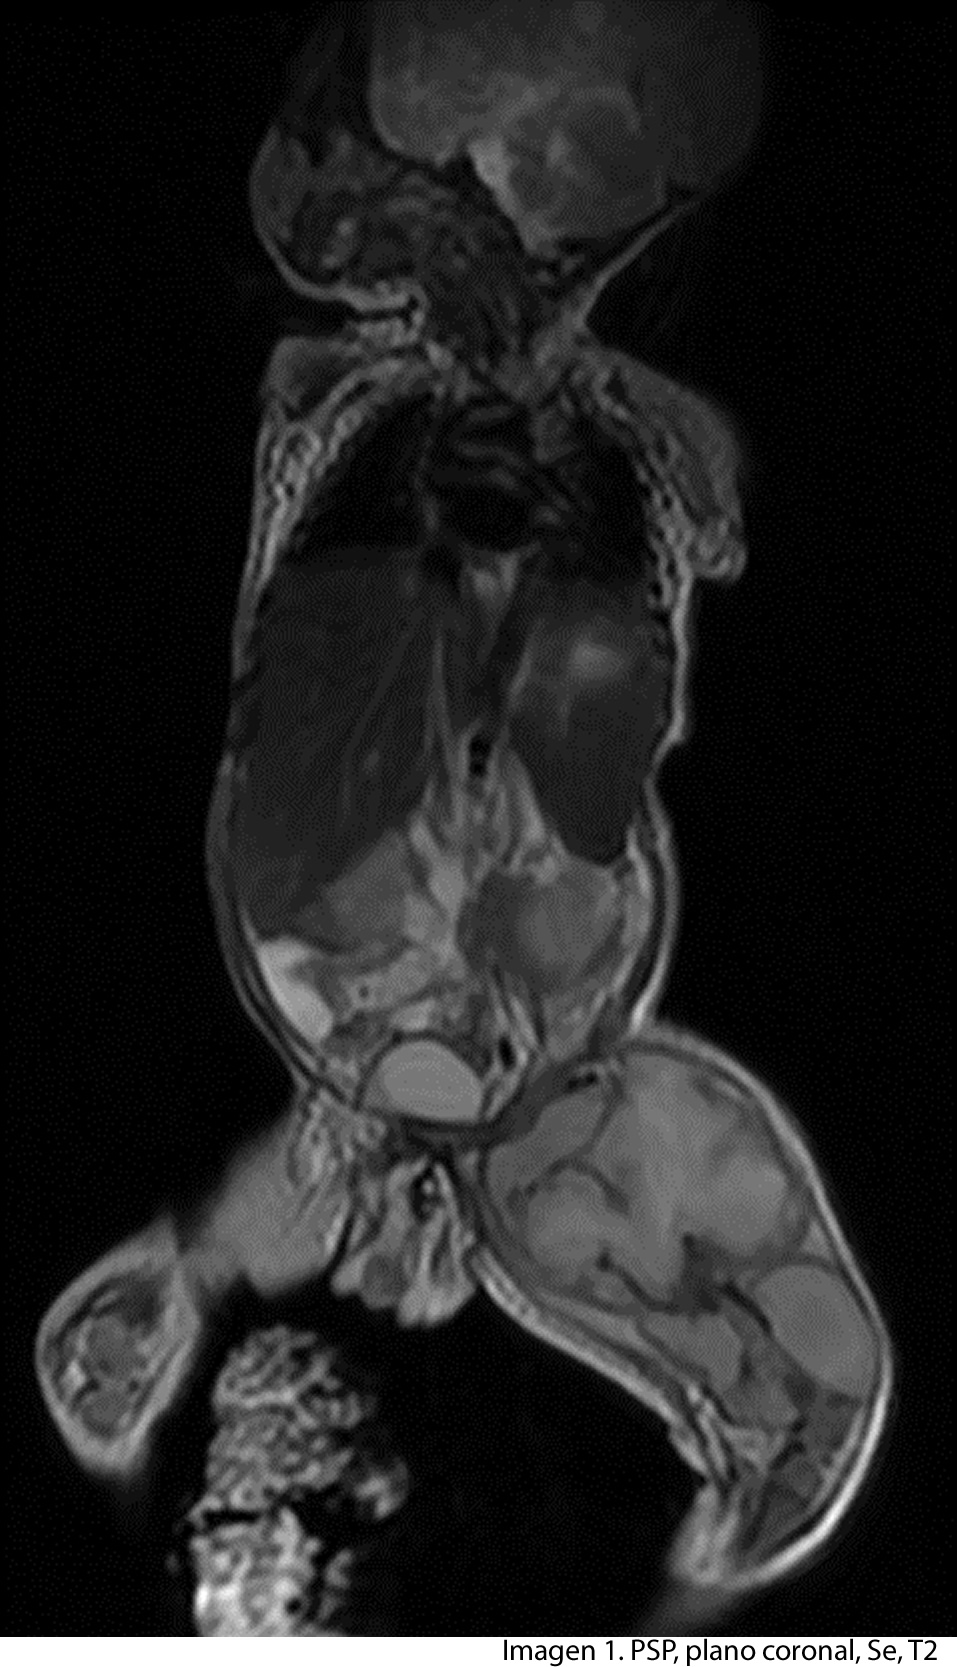

Paciente de 2 años de edad, madre refiere que después de un año de vida inicia con cambios de coloración y aumento de volumen en muslo izquierdo, seis meses después inicia a observar el mismo problema a nivel del hombro izquierdo, por lo que consulta a facultativo, el cual solicita estudio de resonancia de cuerpo entero, enfocado a muslo y hombro izquierdo.

Paciente nace en hospital nacional, sin ningún problema al momento del parto, madre no refiere problema durante el embarazo, indica que al año de vida inicia con aumento de volumen del muslo izquierdo, observa cambio de coloración en el mismo, seis meses después dichos cambios inician a observarse a nivel del hombro izquierdo. No refiere trauma alguno, ni enfermedad severa que lo afecte en los dos años de vida.

Se realiza estudio de resonancia magnética con un equipo de 1.5 tesla, se aplica protocolo de sedación, se utiliza bobina fase arrays, y se procede a adquirir un PSP, en tres planos, secuencias Se, ponderadas a T1 y T2, se administra medio de contraste por vía I.V.

A nivel del muslo izquierdo se observa una colección bilobulada, en la parte proximal se observa imagen que mide 7.05 x 7.17 cms en el tercio distal se observa imagen que mide 3 x 4.01 cms. En la ponderación T2 la lesión se vuelve hiperintensa y en la ponderación T1 con mdc la lesión se vuelve hipointensa con realce de la periferia, lo que confirma la presencia de absceso.

La diáfisis femoral proximal se ve totalmente destruida, a nivel del hombro izquierdo la cabeza del humero no se observa.